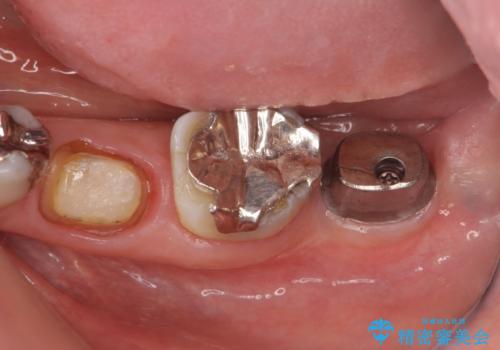

- 左下奥歯の咬合時疼痛を訴えて来院されました。

最後方臼歯周囲には大きな透過像が見られ、破折が強く疑われること抜歯が想定されることを理解していただき銀歯を除去したところ破折が認められたため抜歯を行いました。

今後の機能回復方法としてインプラント治療を希望されたため、将来的に大規模な骨造成が必要とならないよう歯槽堤保存術を抜歯と同時に行いました。